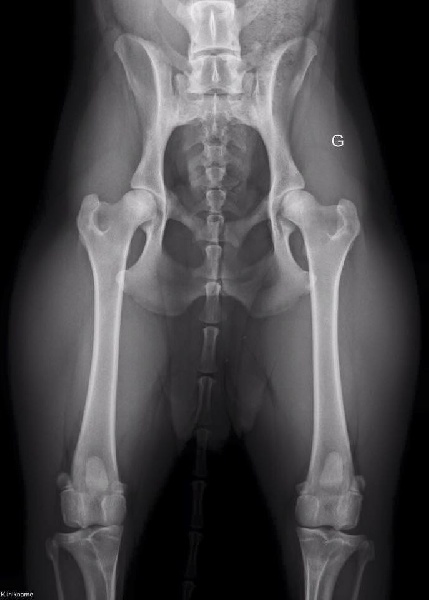

Radio des hanche très bonne attente de lecture

Examen hanche HD : A